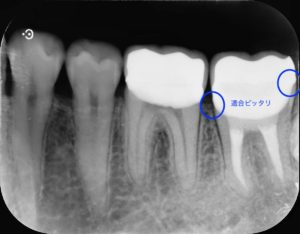

治療前

左下第二大臼歯部に不良補綴物をみとめたため、レントゲン検査を行うと根尖部透過像がみられた。根管内に破折器具がみられたため、破折器具の除去および根管内の感染除去を行った。経過観察後、根尖部透過像の縮小をみとめたため、歯冠修復を行った。

根管治療の偶発症として、使用する器具の破折があります。破折器具は根管治療の妨げになる場合があり、治療中に除去を試みることがあります。根管治療の目的は感染源を取り除くことであり、破折器具そのものが感染源になるわけではありません。そのため破折器具を取り除かなければ病変が治癒しないわけではありません。重要なのは感染源を取り除くことにあります。また、破折器具を取り除くために健康な歯を大きく削らなければいけない場合もあり、破折器具を取り除くことが歯の延命に必ずしも直結するわけではありません。

今回の症例では根管内の汚染が強く、破折器具もはじめからしっかり見えたことから超音波切削器具と次亜塩素酸ナトリウム等を用いて除去しました。再度根管充填を行ったあと、病変の縮小をみとめた後に歯冠修復を行いました。

また根管治療後に適合の良い、再感染の起こりにくいジルコニアセラミッククラウンでしっかり再感染を防ぐことが根管治療の予後を左右します。